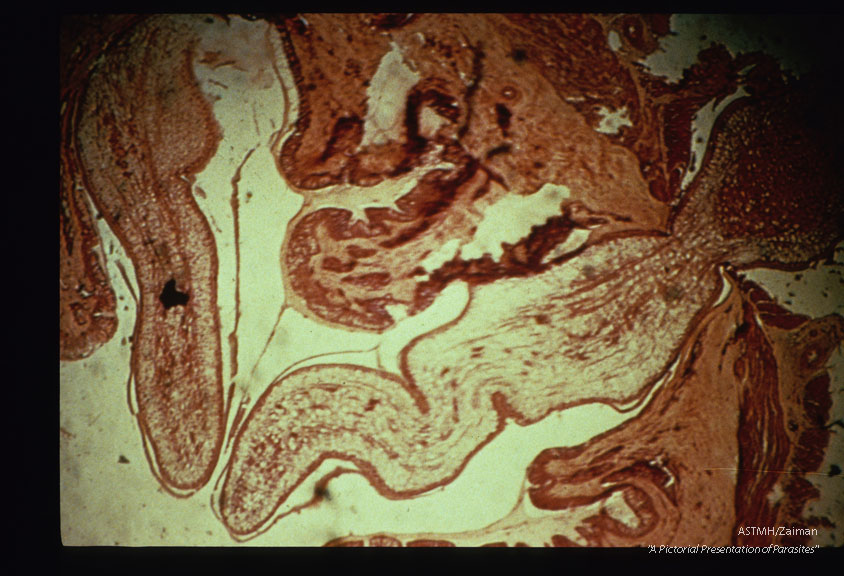

Sparganum perforating cat gut.

Description: Sparganum perforating cat gut.